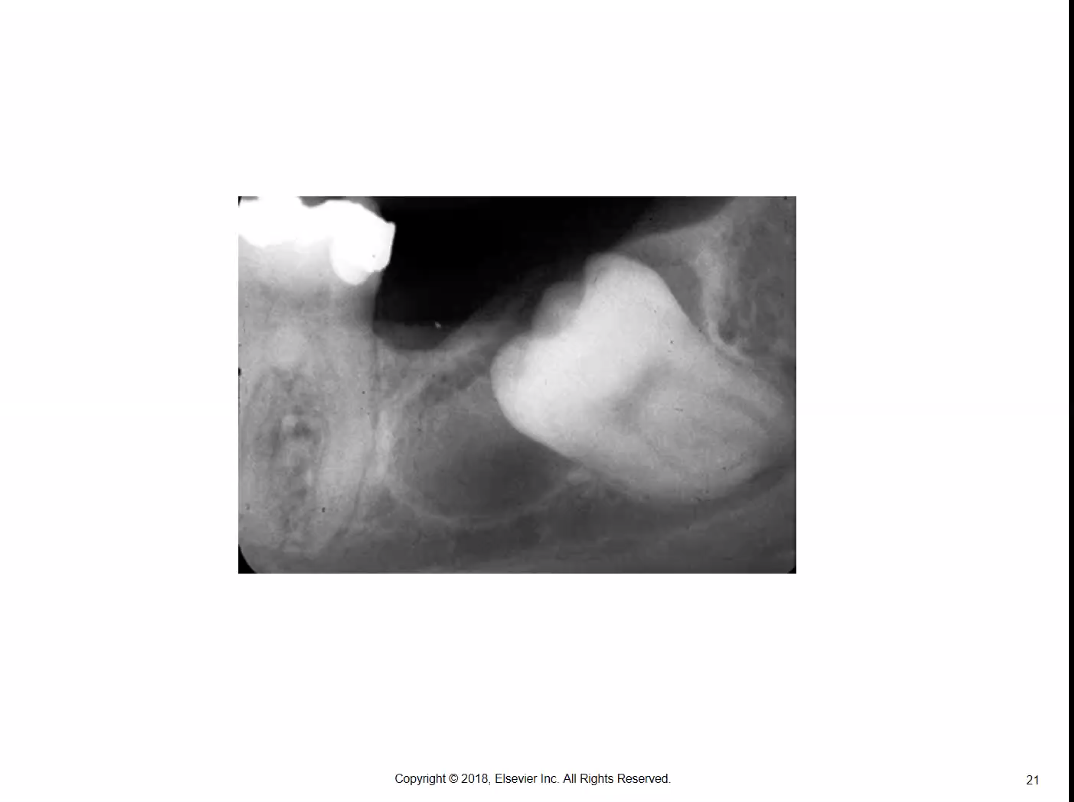

The _____ is characterized by its unique histologic appearance and its frequent recurrence rate.

A) radicular cyst

B) residual cyst

C) dentigerous cyst

D) odontogenic keratocyst

The odontogenic keratocyst is characterized by its unique histologic appearance and its frequent recurrence rate. The radicular cyst is caused by pulpal inflammation. The residual cyst remains after extraction of the tooth with the radicular cyst. The radicular cyst is left behind and not removed. The dentigerous cyst is treated by complete removal of the cyst and the tooth involved.